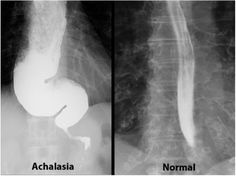

The oesophagus in questions has been damaged by multiple dilations in an attempt to open up the cranky sphincter that in a normal, healthy digestive system, controls food dropping into the stomach and prevents acid leaking out of the stomach. My sphincter – let’s call him Sid – does none of that. Sid basically sits there, irreversibly clenched, like the angriest commuter on a Southern train over the Christmas period*.

Above Sid, is Moo. This is my second stomach, created as my oesophagus has stretched to accommodate all the food and liquid that Sid won’t allow through. Here a mixture of food and stomach acid rots, until it either goes down or comes up. Down is preferable.

Above Sid and Moo, is my oesophagus. This should pulse in order to push food down through the digestive system, technically known as peristalsis. I have nothing from roughly below my voice box. On a good day, it means that I have to drink a lot of water to get food down. On a bad day, food and “debris” gets stuck, causing hours of sickness and reflux as my inanimate throat tries to disloges whatever is making it heave.

So, Sid, Moo and I are seeing in the NY together. With some of the worst of my condition, acalaysia^^, beating another planned evening of happiness to a mushy duvet-wrapped pulp. Full on FOMO included.